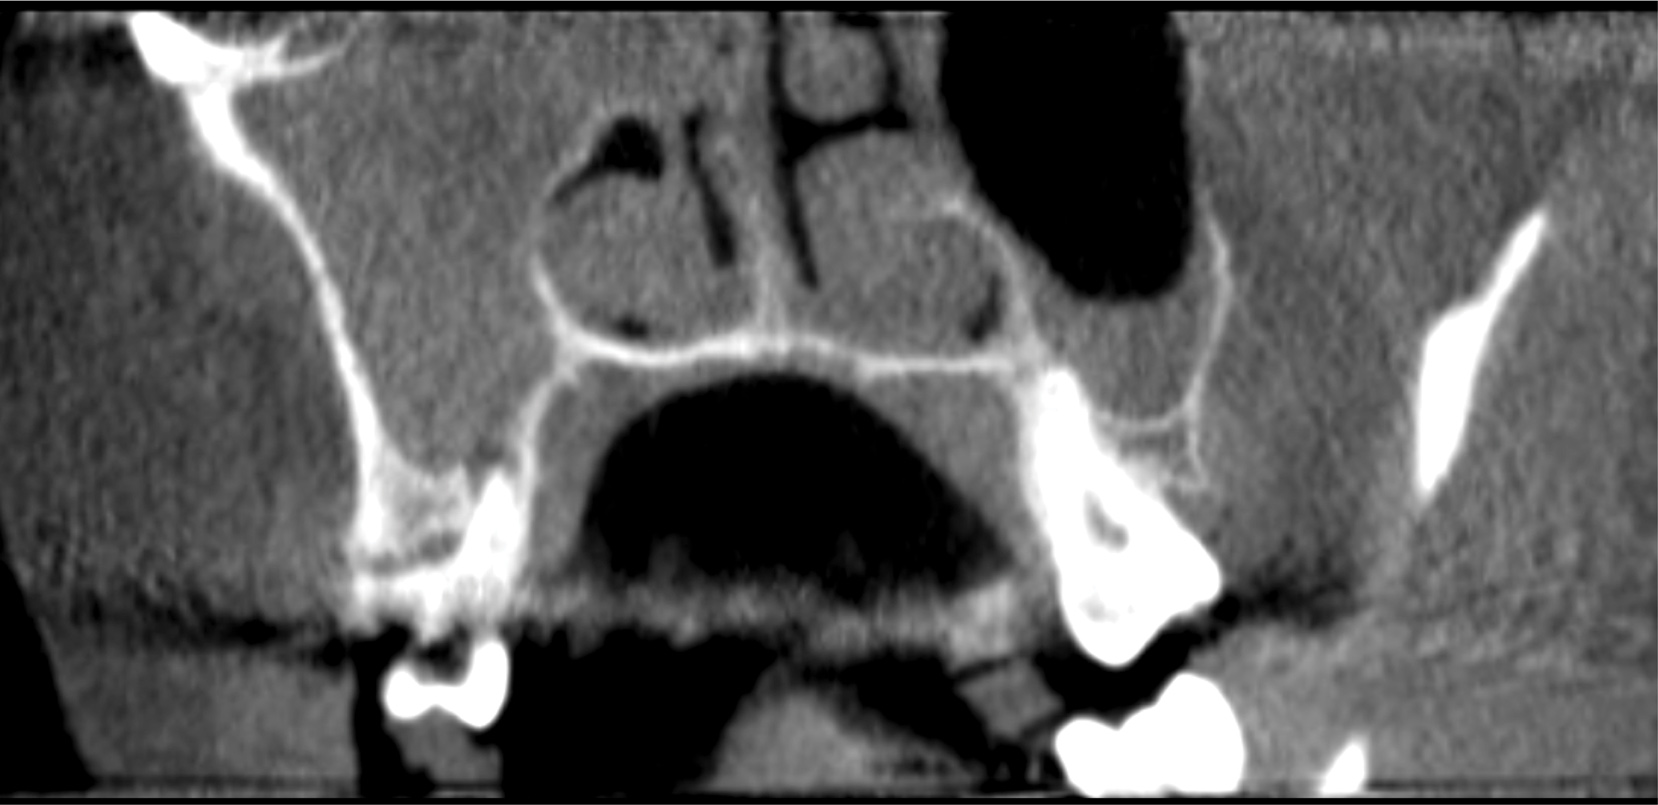

A 58-year-old female patient presented to the office with a 3-month history of acute sinusitis, during which six courses of antibiotics, including penicillin, cephalosporin, and quinolone drugs, had failed to resolve her symptoms. She had been referred for endodontic evaluation by her ENT specialist after imaging revealed endodontic pathosis of tooth No. 2. On initial presentation, tooth No. 2 was nonvital (ie, nonresponsive to cold or electric pulp testing), tested positive to percussion and palpation, and was without swelling, sinus tracts, or periodontal defects. The preoperative CBCT scan revealed apical pathosis on the buccal and palatal roots of tooth No. 2, complete opacification of the right maxillary and ethmoid sinuses, and disruption of the lateral/posterior antral wall posterior to the zygomaticomaxillary buttress (Figure 6). Root canal therapy was initiated. Upon access, black staining of the pulp tissue was observed, indicating necrosis. Pulpal debridement was performed, and calcium hydroxide was utilized as an intracanal medication. Several weeks after pulpal debridement, the patient's sinus symptoms improved, but incompletely. Tooth No. 2 was obturated, and the patient was referred to an ENT specialist for further care.

(6.) Preoperative CBCT image showing periapical pathosis of tooth No. 2 in communication with the sinus.

Figure 6